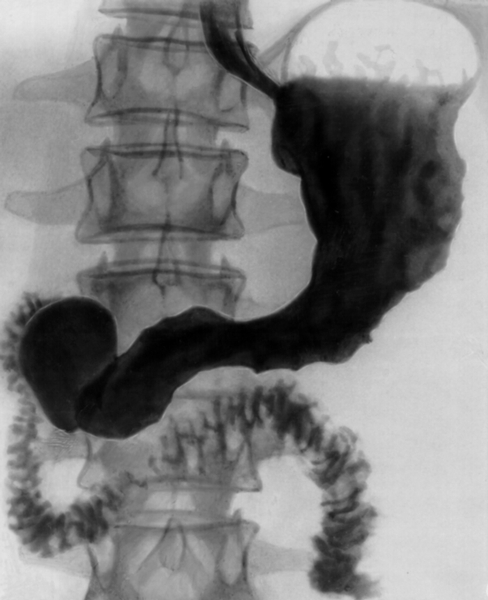

- В некоторых случаях можно исследовать кишку при помощи ирригоскопии (Приложение 2.3).

- Диагноз ставят на основании результатов рентгенологического исследования (при ирригоскопии с двойным контрастированием видны множественные дефекты накопления);

- Часто случается, что пищевод настолько сужен из-за находящейся в нем опухоли, что эзофагоскоп не проходит. В таком случае для диагноза используется рентгенологическое исследование (Приложение 2.1), при котором пациент должен выпить особую смесь бария, и затем выясняют места препятствий и размер опухоли.

- Используется рентгенологическое исследование желудка со смесью бария (Приложение 2.2);